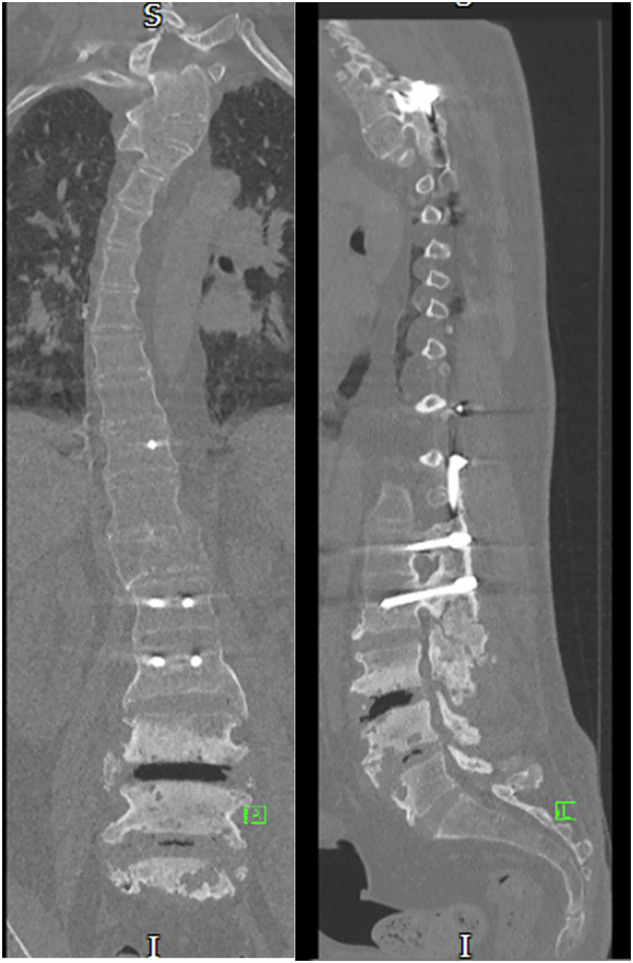

研究设计:回顾性分析6例Charcot脊柱关节病。目的:评价Charcot关节病的病因、临床表现(如疼痛、躯干不稳、自主神经反射障碍、痉挛)、症状发作前潜伏期、脊柱受累区及治疗策略。地点:英国国家脊髓损伤中心。方法:对6例确诊为Charcot型脊柱关节病的患者进行资料收集和分析。检查的变量包括病因、临床表现、受影响的脊柱区域、潜伏期和治疗方法的结果。对保守治疗和手术干预策略进行了评价。结果:患者均表现为疼痛、躯干失去控制、自主神经反射障碍、痉挛等常见临床表现,症状发作前潜伏期不同。胸椎是最常见的受累部位。在大多数病例中,保守治疗成功地稳定了症状,而在严重的躯干不稳定、难治性疼痛或影响活动的畸形的情况下,手术干预是必要的。结论:保守治疗应是沙尔科关节病的首选治疗方法。手术干预保留给有重大临床进展的病例,如未解决的疼痛,躯干畸形导致的活动受限,或脊柱病理引起的紧急并发症。

Results: Patients exhibited common clinical manifestations such as pain, loss of trunk control, autonomic dysreflexia, and spasticity, with varying latency periods before symptom onset. The thoracic spine was the most frequently affected region. Conservative management successfully stabilized symptoms in most cases, while surgical intervention was necessary in instances of severe trunk instability, refractory pain, or deformity impacting mobility.